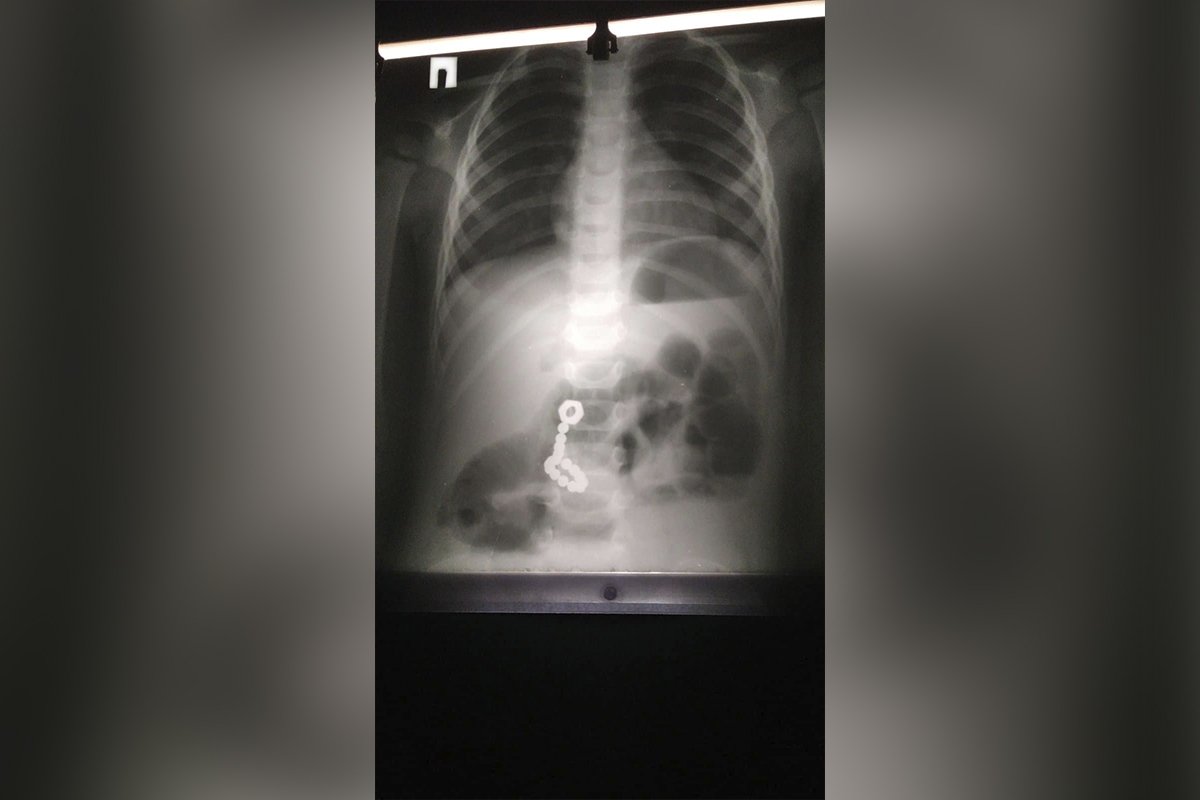

Как выяснили медики, мальчик проглотил детали головоломки. Об этом Информатор сообщает со ссылкой на публикацию в Facebook Днепропетровской областной детской больницы.

«Сложность оперативного лечения заключалась в том, что шесть магнитов находились на разных уровнях желудочно-кишечного тракта: в тонком кишечнике и в просвете двенадцатиперстной кишки. Большей беды, слипания стенок кишечника, удалось избежать. Однако 5 дней, проведенных с малышом в реанимации, мама с папой запомнят на всю жизнь: оперативное вмешательство пытались провести с максимальной минимизацией рисков для пациента, но маленькие детали успели продырявить кишечник, а некоторые пораженные участки вообще почернели – такова сила сжатия этих магнитов», - сообщили в больнице.